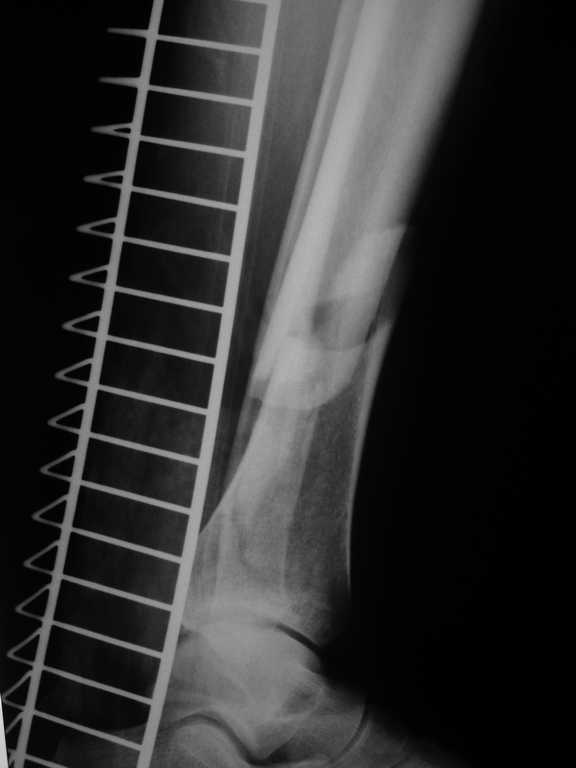

48 yo male, crush injury (esp. Gustilo IIIA ) of distal tibia managed nonoperatively ( cast ! ABX) for 2 days, was transferred to us.

There,s no signs of infection but condition of skin is bad ( large contusion, Tscherne 3 ) What kind of treatment: definitivly or staged ? Internal fixation (plate) or maybe nail + screws ? Ilizarov is an option... <br>

Имя     : DSC04434.JPG